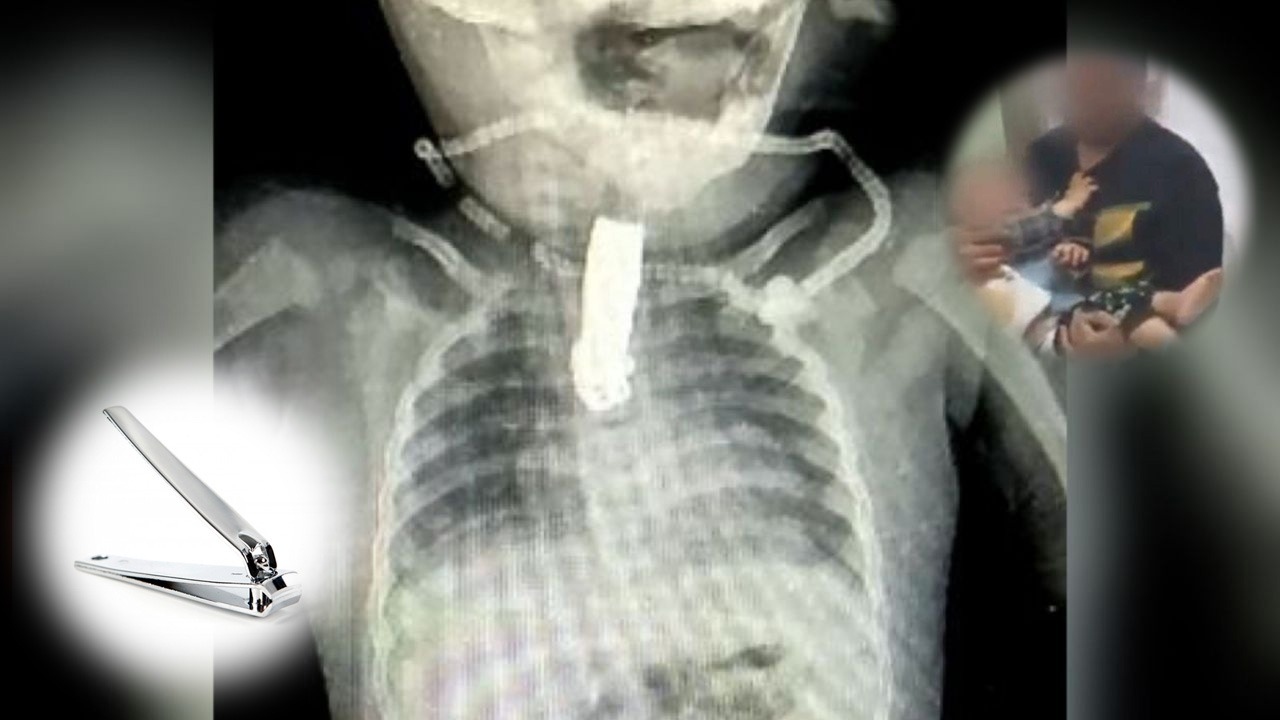

Extraen de la garganta de una bebé un cortaúñas de cinco centímetros

Una niña de 8 meses estuvo a punto de morir ahogada luego de tragarse un cortaúñas de cinco centímetros el cual le habían dado sus padres para entretenerla.

Los progenitores se descuidaron y la niña se introdujo el instrumento en la boca y terminó tragándoselo y se quedó atorado en su garganta.

La bebé fue sometida a una delicada cirugía puesto que se trataba de un objeto punzocortante.

Los médicos confirmaron que la operación que duró una hora fue un éxito, puesto que sacaron el cortaúñas sin mayores complicaciones.

El accidente quedó en susto, los doctores destacaron la rapidez de los padres ya que de haber esperado el desenlace habría sido fatal.